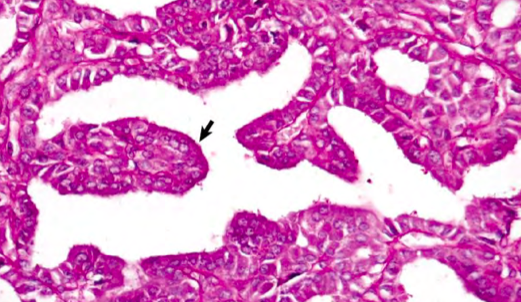

Conn’s syndrome

Cat with “Conn’s syndrome”

Mineralocorticoids

Signs due to hyper- aldosteronism

Hypertension

Polymyopathy – due to hypernatremia and hypokalemia